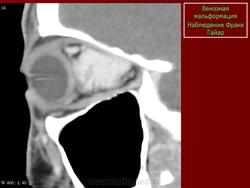

Лимфангиома орбиты (син.: сосудистая гамартома, венолимфатическая мальформация)

Врожденная доброкачественная сосудистая опухоль, которая состоит из расширенных сосудов, окруженных лимфатической тканью.

В большинстве случаев ограничивается конъюнктивой. Лимфангиомы орбиты прогрессивно увеличиваются в размерах, не склонны к спонтанной инволюции. В отличие от капиллярных гемангиом, которые часто подвергаются обратному развитию. Составляют менее 5% опухолей глазницы у детей. Могут сочетаться с лимфангиомами других локализаций. В норме в глазнице лимфатическая ткань не определяется.

Наиболее типичная черта: выявление уровней жидкости в образовании, за счет спонтанных кровотечений.

Экстраорбитальное (но может быть рапсоалагаться как в канале, так вне его), мультикистозное, мультифокальное объемное образование с неправильным контуром.

Гиперденсное, по плотности сопоставимо с мышечной тканью, негомогенной структуры образование, пересекает анатомические границы. Стенка лимфангиомы вариабельно накапливает КВ. Тип краевого накопления КВ иногда позволяет установить умеренное ремоделирование прилежащей кости. В структуре образования иногда определяются небольшие кальцинаты или флеболиты.